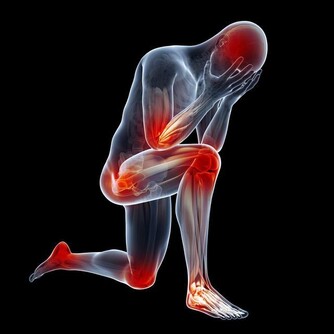

30歲開始,關節痠、痛、軟!

關節退化,是免不了的老化過程。

運動過度、關節受傷、過度肥胖等,都會使關節提早退化,

而膝關節、髖關節、脊椎等,是最容易退化的關節部位。

你知道嗎,我們的關節每天所承受的壓力有多重?

其實除了平躺的時候,其他時候膝蓋一直都在負重。

有研究指出,

走路時膝蓋所承受的重量,是體重的1~2倍;

上樓梯則多增加1倍,變成3倍;

跑步時,更要承受4倍的重量,實在令人難以想像!

健康的關節要達到穩定且可大範圍的活動,

有賴於完整的骨頭、控制良好的肌肉、健全的神經系統、穩固的韌帶等條件配合,

只要任何一個環節出問題,關節就無法正常活動,

進而產生疼痛、活動不良、行動不穩定等問題。

關節在長期承受壓力及運動下,表面的軟骨會逐漸失去彈性,

且因不斷地磨損,使軟骨的厚度減少,關節間隙會變得狹窄,

當行走或運動時,

所產生的力量會直接作用到軟骨下方的骨頭,逐漸使之產生變化,甚至壞死。

加上軟骨是一多孔的結構,

因老化使得膠原蛋白變少而失去保護力,就會促使關節變形而加速磨損。